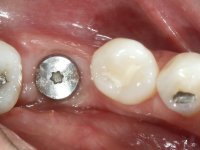

Paciente do sexo feminino, com 36 anos de idade, não fumadora. Apresentava o dente 1.1 com uma tonalidade mais escura que os dentes adjacentes. Feito o exame imagiológico, observou-se que o dente 1.1 tinha tratamento endodôntico, a paciente tinha 3 implantes colocados, dois no local dos dentes 1.2 e 2.2 e o outro no 4.6. A paciente tinha sido tratada ortodonticamente, apresentava um fenótipo gengival médio e uma boa higiene oral. Após 5 anos da primeira intervenção a paciente apresenta-se na consulta com sintomatologia infeciosa compatível com uma peri-implantite nos implantes 1.2 e 4.6. Após exame clínico, foi confirmada imagiológicamente. A perda óssea vertical tinha mais de 4mm nas duas situações.

Após 5 anos da primeira intervenção, a paciente surge na consulta com uma peri-implantite nos implantes colocados no local dos dentes 1.2 e 4.6. Começamos por abordar a peri-implantite no local do dente 2.2. Foi feita uma ponte provisória de laboratório em acrílico com 2 elementos. O dente 1.1 como pilar e o 1.2 como pôntico, este último apresentava um apoio distal. A coroa do 1.2 foi removida do coto com um corte longitudinal feito com turbina e depois foi fraturada com um mini luxador. O coto foi de seguida desaparafusado do implante. Fez-se o mesmo procedimento para remover a coroa do 1.1. O dente 1.1 foi re-preparado e a ponte provisória foi rebaseada em boca com acrílico autopolimerizável. Feito o correto acabamento e polimento da provisória foi feita a sua cimentação temporária com cimento de policarboxylato. Numa consulta posterior. foi feita a remoção da ponte provisória, feita a cirurgia para explantação do implante, colocou-se um novo implante e fez-se a regeneração óssea da zona com uma membrana não reabsorvível. 3 meses após foi removida a coroa do implante colocado no 4.6. Foi feito um corte horizontal com turbina na zona cervical e com um mini luxador descolou-se a coroa do coto. Após este procedimento fez-se a explantação do implante. Após 6 meses foi colocado um novo implante no local do 4.6. Após a osteointegração foi feita a impressão com a técnica de moldeira aberta e foi confecionada em laboratório uma coroa aparafusada sobre o implante. Aprovada pela paciente foi apertada definitivamente em boca. Após 1 mês removemos a ponte provisória antero-superior, reforçamos o dente 1.1 com um poste intra- radicular e reconstruimos o coto com uma resina de polimerização dual. Nessa mesma consulta expomos o implante colocado no 1.2 e fizemos uma impressão pela técnica de moldeira aberta com silicone de dupla viscosidade e presa rápida. No laboratório foi feita uma ponte provisória de 2 elementos, aparafusada sobre o implante e cimentada sobre o dente. A primeira ponte provisória foi removida e colocada a segunda aparafusada sobre o implante. A linha de acabamento cervical do 1.1 foi rebaseada com resina composta durante o aperto do parafuso do implante. Depois foi removida, foram feitos os acabamentos e finalmente apertada sobre o implante e cimentada temporariamente sobre o dente. Após 2 meses de maturação dos tecidos moles em função do perfil de emergência criado pela nova ponte provisória, pudemos avaliar a estética conseguida em conjunto com a paciente. Neste longo processo o dente 2.1 teve que fazer um tratamento endodôntico. Decidiu-se assim fazer também uma coroa no dente 2.1.O dente 2.1 foi preparado na mesma consulta em que se fez a impressão ao implante. A ponte provisória foi utilizada para individualizar a peça de transferência, copiando o seu perfil de emergência e em seguida foi realizado o afastamento gengival com caolino. A impressão foi feita com a técnica de moldeira aberta com silicone de dupla viscosidade e presa rápida. Após a escolha da cor, a impressão foi enviada  para o laboratório onde foram confecionadas 2 coroas  com infraestrutura em Zr. revestidas a cerâmica para os dentes 1.1 e 2.1 e uma coroa aparafusada sobre o implante no dente 1.2. O trabalho final foi aprovado pela paciente e foi colocado definitivamente em boca. A coroa sobre o implante foi aparafusada com 35 N e as coroas foram cimentadas com cimento de ionómero de vidro reforçado com resina.